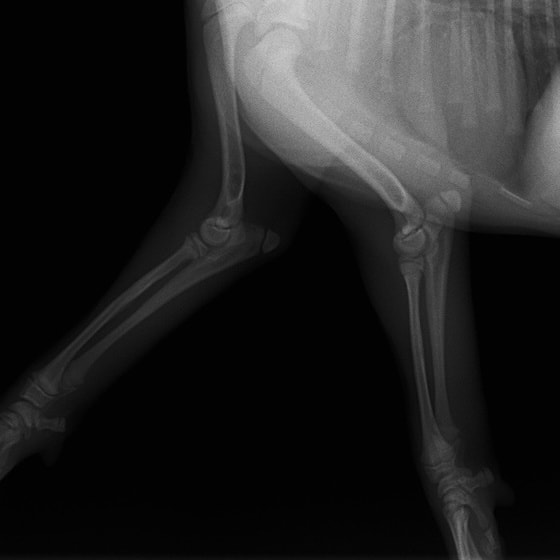

ペルシャ猫 11ヶ月齢 雄

他院にて左大腿骨遠位の成長板骨折(salter-harrisⅠ型)が認められており、治療相談を目的として来院。当院にて、キルシュナーワイヤーを用いたピンニングにより骨折部位の整復を行いました。術後の経過は良好で、現在も経過観察中です。

術前レントゲン